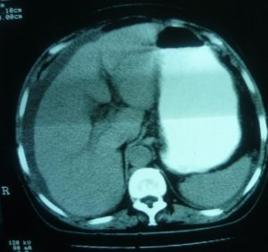

正常CT表現:

胰腺頭、體、尾在同一層面,形態及大小均正常。十二指腸環包繞胰頭,主動脈、腸系膜上動脈及脾靜脈均清晰可見。